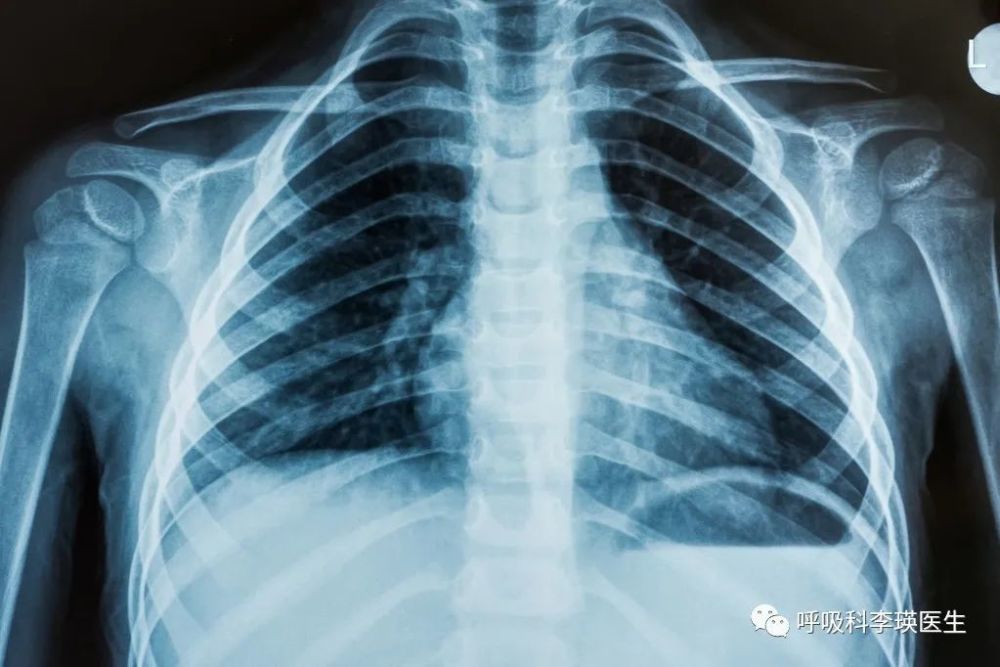

颈部的淋巴结肿大所导致的原因是不多的 , 年轻人最常见的是淋巴结结核 , 淋巴瘤 , 老年人比较常见的是癌症肺癌淋巴结转移 。 于是我给他做了一个肺部ct , 就发现他的右侧的胸腔有大量的胸腔积液 , 并且胸膜增厚已经差不多有一个厘米了 。